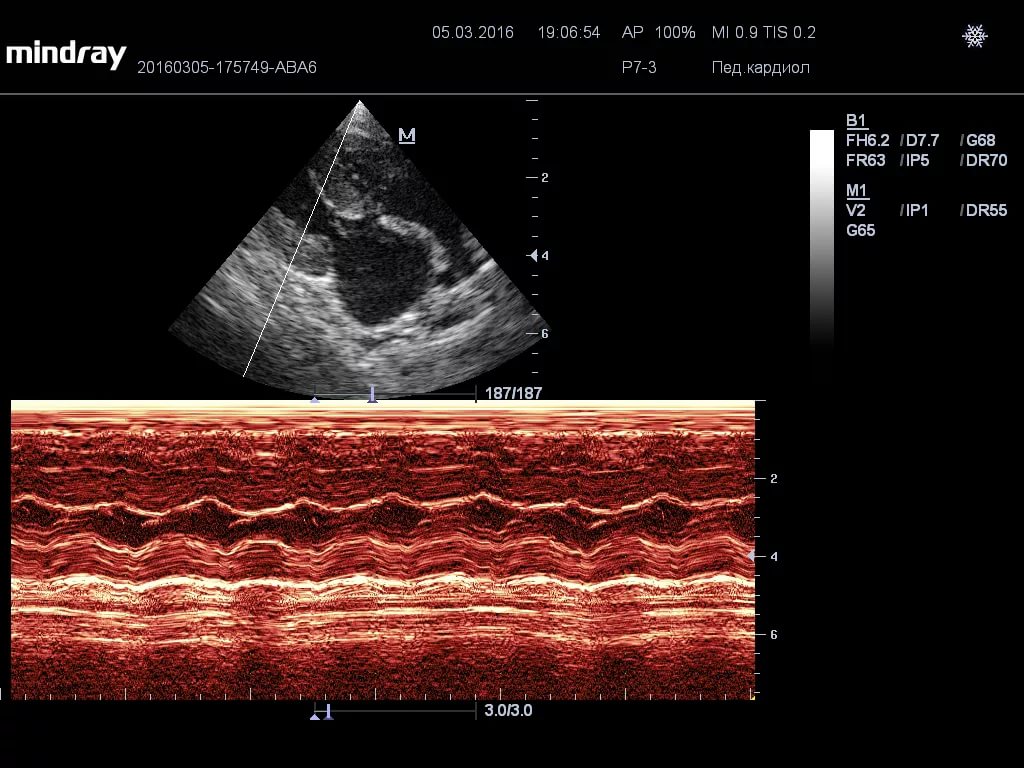

Ngoài các bệnh này, Scottish Folds còn được đặc trưng bởi các bệnh khác điển hình cho các giống mèo còn lại: da (bệnh nấm, áp xe, áp xe, loét, phát ban, dị ứng), bệnh truyền nhiễm (bệnh salmonella, bệnh dại, bệnh thiếu máu, bệnh candida) (giãn đồng tử, đường rách, lõm ống kính), bệnh tim (bệnh cơ tim phì đại), cũng như một số bệnh ung thư.

Bệnh cơ tim phì đại